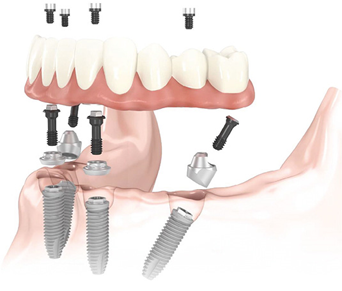

Несъемное протезирование при ПОЗ с успехом реализуется на 5-6 внутрикостных имплантатах в фронтальном отделе челюсти путем конструирования укороченного зубного ряда протеза. Исследования P. Branemark показали более высокую функциональную эффективность таких протезов по сравнению с ПСП. В ряде случаев при высокой первичной стабильности имплантатов возможно применение меньшего числа имплантатов для опоры несъемного протеза, т.е. реализация методики All-on-4, при которой установка крайних имплантатов вынужден-но производится с наклоном для профилактики травмирования n. mentalis и sinus maxillaris (рис. 2.9.11). Небольшое число опорных имплантатов, нагрузка "под углом" крайних имплантатов и реализация в этой методике немедленной нагрузки имплантатов в совокупности повышают риск функциональной перегрузки костной ткани, что обусловливает важность соблюдения показаний к такому протезированию и его планированию, а также необходимость контроля функциональной нагрузки и гигиены в период эксплуатации протеза All-on-4. Особенностями протезирования по методике All-on-4 являются: немедленная нагрузка имплантатов временным несъемным протезом с винтовой фиксацией к имплантатам; использование специальных абатментов multi-unit для компенсации наклона имплантатов; укороченный зубной ряд; протез на основе металлической балки (каркаса) с искусственными композитными или керамическими зубами.

image

Рис. 2.9.11. Концепция протезирования на имплантатах All-on-4

Абатменты multi-unit, прямые и угловые, используются для опоры условно-съемных протезов с разным числом опорных имплантатов (рис. 2.9.12).

Рис. 2.9.12. Абатменты multi-unit: а - прямой; б - угловой